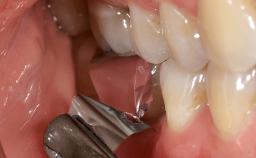

Surgical Management of Peri-Implantitis: Open-Flap Debridement with Seven-Year Follow-up After Treatment

This case describes both a surgical and an anti-infective approach for the management of peri-implantitis, including treatment of the entire dentition to eliminate any deep periodontal pockets that could serve as reservoirs for bacterial re-colonization at the implant site. A 65-year-old female patient was referred to the periodontist in 2013 for assessment and management of an infection at implant 12. On examination, probing depths at implant 12 were 11 mm with suppuration and bleeding on probing.